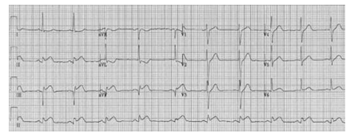

Um paciente de 62 anos de idade, previamente hipertenso, apresentava dor torácica típica já há 2 horas, irradiando para o braço esquerdo, associada à sudorese e às náuseas. No exame físico, apresentava-se estável hemodinamicamente. O eletrocardiograma de admissão está disposto logo a seguir. O paciente chegou ao serviço médico às 19 horas, na troca de plantão, passando-se, assim, 45 minutos sem reavaliação. O paciente estava em um hospital sem serviço de hemodinâmica, e o centro de referência mais próximo tinha um tempo estimado de recebimento do paciente em 80 minutos.